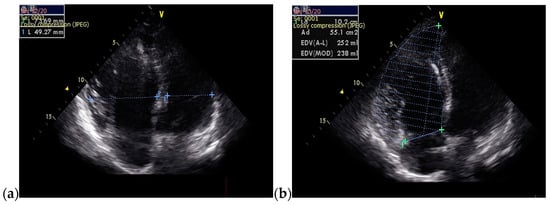

A 36-year-old non-smoker male patient, without cardiological follow-up and no cardio-active medication at home, presented with dyspnea, mild effort intolerance, and headache. Physical examination revealed peripheral cyanosis, body mass index (BMI) = 27.68 kg/m2, blood pressure (BP) = 115/70 mmHg, heart rate (HR) = 75 bpm, and unremarkable cardiac and pulmonary auscultation. The electrocardiogram showed sinus rhythm, HR = 75 bpm, rSR’ pattern in precordial leads V1 or V2 (Figure 1a). The chest radiography revealed a normal heart size with hilar bilateral enlargement and increased vascular density in the upper half of the hilum (Figure 1b).

Figure 1.

(a) 12-lead ECG revealed sinus rhythm and rSR’ pattern in precordial leads V1 or V2; (b) Postero-anterior chest view radiography showed hilar bilateral enlargement and increased vascular density in the upper half of the hilum. Abbreviations: ECG—electrocardiogram.